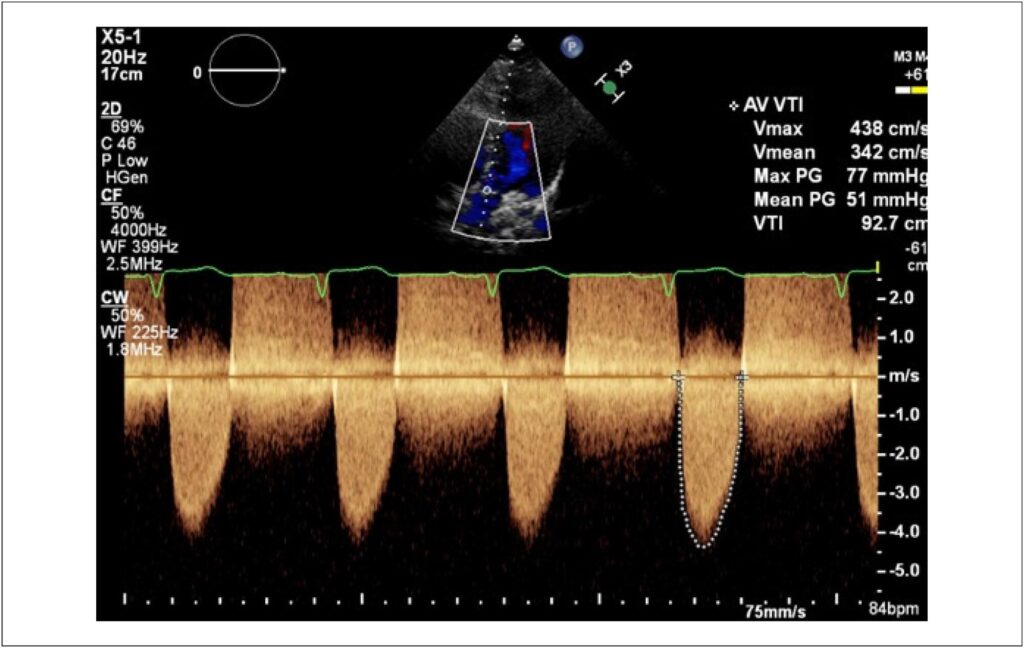

A valva aórtica unicúspide (VAU) é uma patologia congênita incomum, descrita pela primeira vez por Edwards, em 1958. Constitui malformação rara (principalmente quando comparada a outras anomalias valvares aórticas), com incidência estimada em 0,02% de adultos submetidos a ecocardiografia, e aproximadamente 4% a 5% de pacientes submetidos a cirurgia por estenose aórtica. A ecocardiografia é o método de primeira escolha em seu diagnóstico e definição de repercussões hemodinâmicas. Neste trabalho, relatamos o caso de uma paciente portadora de estenose aórtica sintomática, bem como a descrição de seu diagnóstico e condução terapêutica.